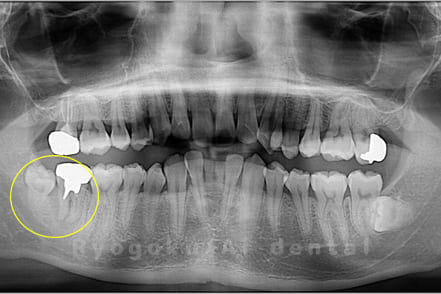

Case10

- 右下6番 重度カリエス

- 右下8を右下6へ移植に自家歯牙移植

- 治療期間

-

- 220,000円

右下の銀歯が外れかかっているとのことでご来院された患者様です。虫歯が大きく、かつ歯が割れており、保存不可能と判断し、親知らずの移植を行いました。

<リスク・副作用>

治療後、痛みや違和感、出血、腫れなどが出る事があります。喫煙者、糖尿病などの方の場合、歯が生着しない場合があります。